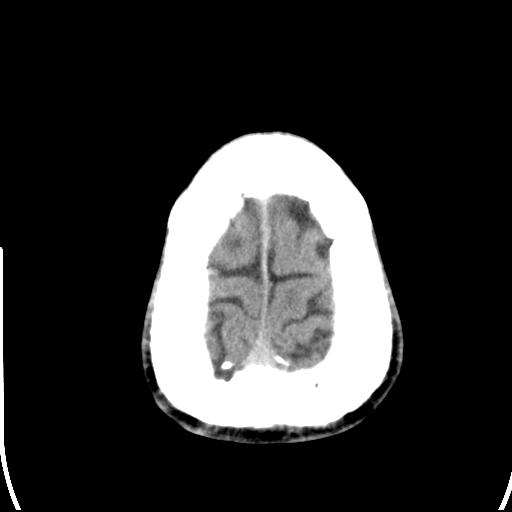

标题: CT25435:头皮下高密度影???

头皮下高密度结节影???临床上在老年男性比较常见。大家看看是什么?成因是? 本例患者,男性,51岁。外伤来诊。无染发史及发根植入史。

考虑异物。

皮下钙化点

没见过,可能为毛囊钙化。

考虑钙化。

这种东西有时要结合触诊和望诊。